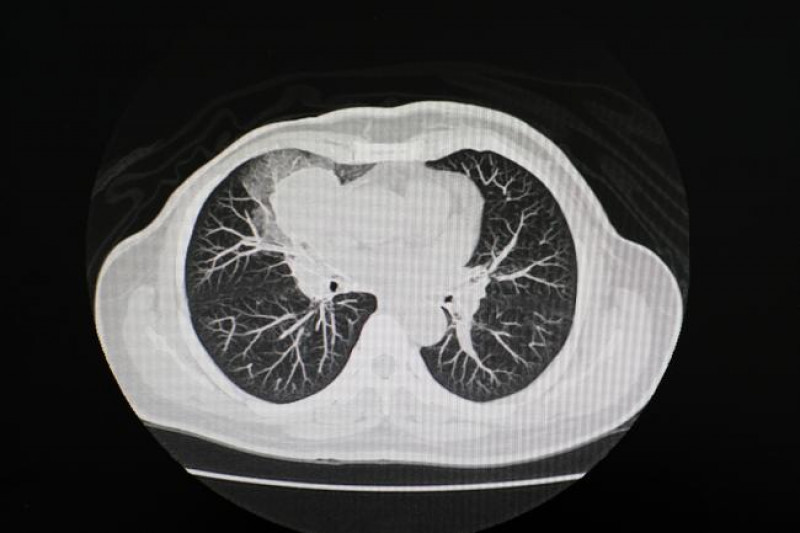

#AIinHealthcare #MedicalImaging #ChronicDiseaseDetection

www.nih.gov

Automated CT scan analysis could fast-track clinical assessments

NIH-funded research suggests AI-powered tool could streamline diagnoses and unveil early markers for chronic disease.

A research team funded by the National Institutes of Health (NIH) has developed a versatile machine learning model that could one day greatly expand what medical scans can tell us about disease.